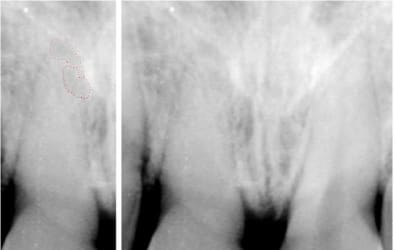

Quelles sont les chances de succès d'un blanchiment interne sur cette coloration due à un choc (pas de réaction aux stimuli thermiques,asymptomatique,disparition totale de la chambre et du canal)

pas de chbre et de canal visible:où mets tu ton perborate? ds un logement que tu fais arbitrairement?

Je peux poser une question idiote et risquer de subir encore des foudres? Mais tant pis j'aime bien avoir les réponses: n'y a t'il pas un trait de fracture niveau collet entre les deux "v" sombres dans les espaces interdentaires, en biais? sur la 11.

... non; et si c'était le cas, avec une fracture à ce niveau, elle serait mobile +++

> enfin parce que l'apparente résorption interne au niveau radiculaire, tout comme ce qui devrait

c'est une obliteration canalaire suite a un trauma(subluxation,intrusion...),la lumiere canalaire s'est remplie d'osteodentine

la lésion apicale, on s'assoit dessus?

C'est pas une fracture mais l'image du nez!

Regarde sur la controlaterale y'a la meme image